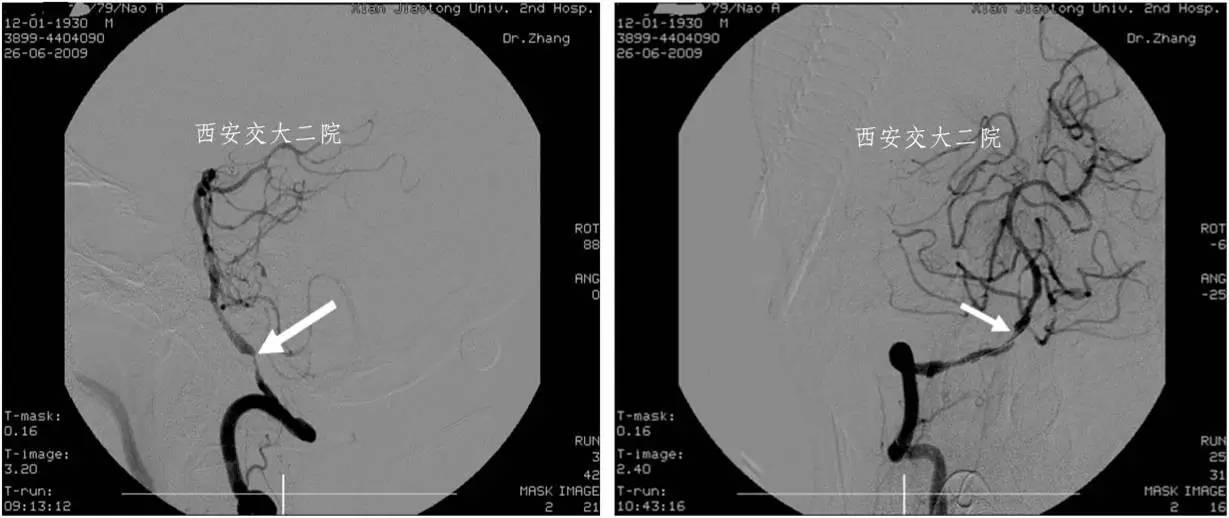

术前DSA

术后DSA